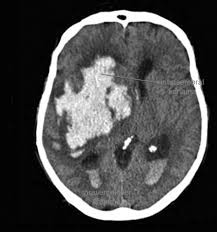

Doktorunuz semptom ve bulguları değerlendirdiğinde hidrosefaliden şüphelenirse tanıyı koymadan önce ayrıntılı bir şekilde hastalığın gidişatını öğrenmeli, ayrıntılı bir fiziksel ve nörolojik inceleme yapmalı, CT veya MRG ile görüntüleme yapmalıdır. Tetkikler sonucunda hidrosefali teşhisi konursa hasta daha ileri tetkik ve tedavi için beyin cerrahi uzmanına refere edilmeli.